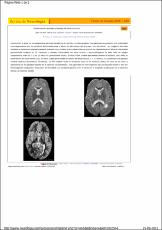

INTRODUCTION: Despite early dietary therapy, many patients with galactosemia show a neurodegenerative disease specially evident in speech impairment and movement disorders. Magnetic resonance imaging of the brain, show cerebral white matter changes with hypomielinization bilateral and symetrical periventricular hypersignal in T2.

RESULTS: The brain MRI showed the typical involvement of white matter, in five children, and basal ganglia abnormalities in the kernicterus patient. Three patients are homozygous for Q188R mutation and two are compound heterozygous.